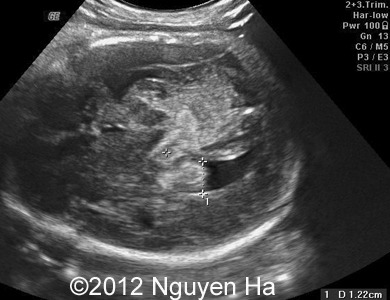

Figures 8-15: 4 days later - 37 weeks of pregnancy.

Figure 8-15: 4 days later; image 1-4 suggesting a middle cerebral artery infarction with formation of schizencephaly, no more cortex at the level of the insula.